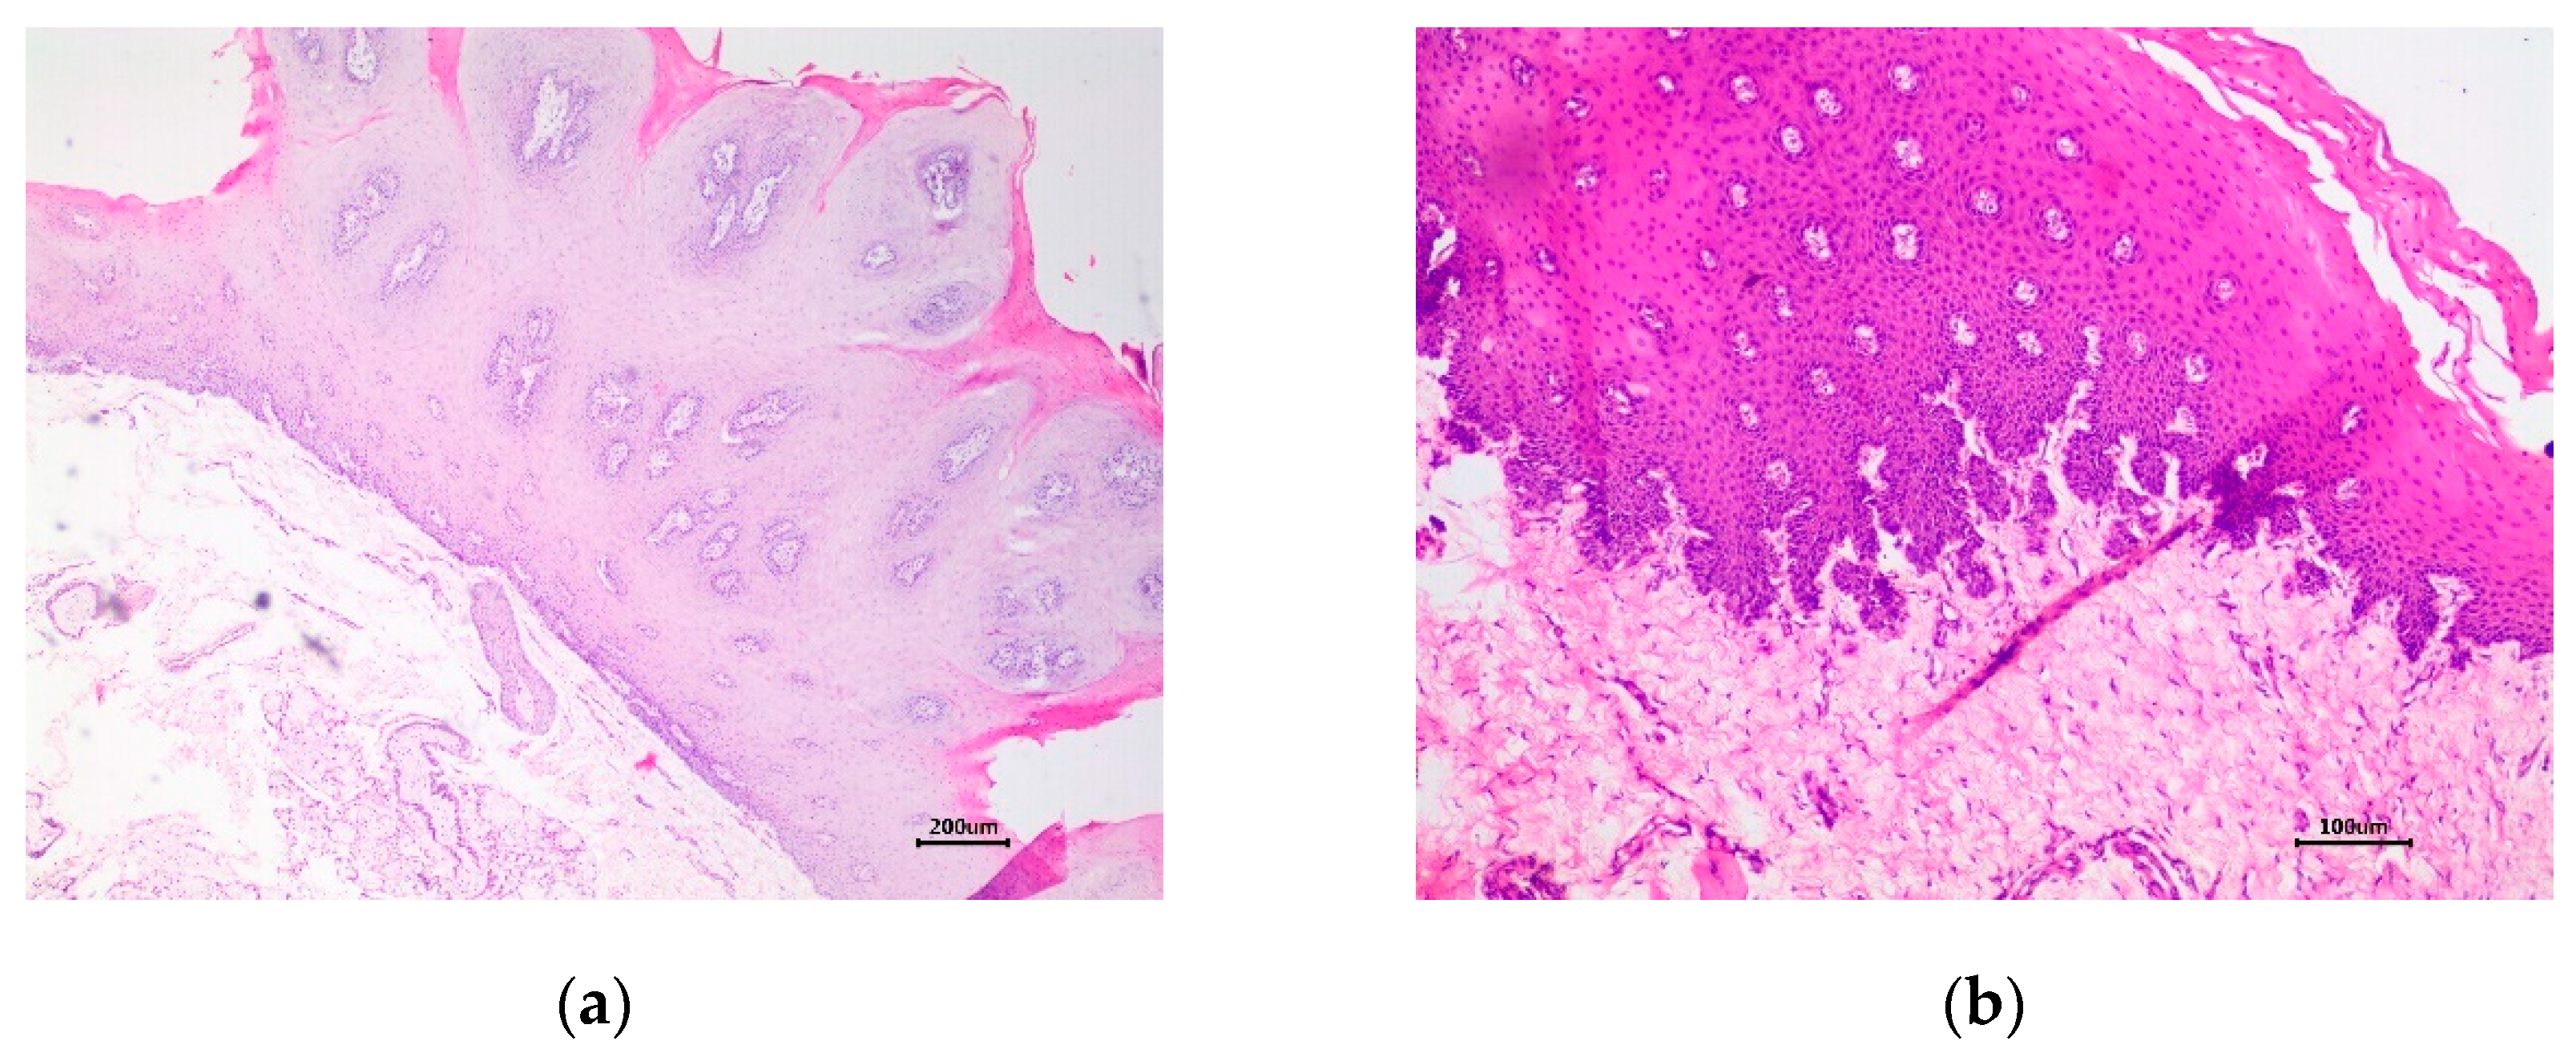

| Squamous papilloma | BPV4 partial L1 gene | BPV4 partial E1 gene | BPV4 complete genome |

| Carcinoma in situ | BPV2 partial L1 gene | BPV2 partial E1 gene | BPV2 complete genome / BPV4 partial sequences of L1, L2, and E7 genes (mixed infection) |